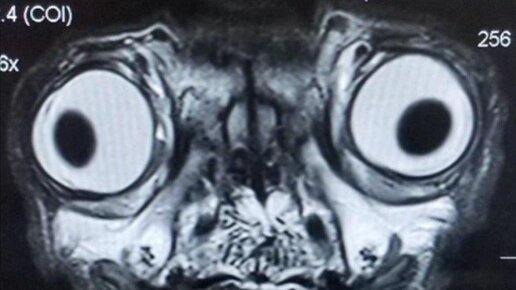

МРТ-скан мопса

Отвлекитесь от людей, сейчас расскажу (на мой взгляд) о неэтичности разведения некоторых пород собак. Я мог где-то ошибиться, так как не ветеринар, но большая часть из вышесказанного — правда. Это — МРТ-скан мопса. Сейчас мопсы выглядят такими "милыми" из-за селекции. Плата за внешность высока: складки...

Менингоэнцефалит у мопса возрастом 4 года.